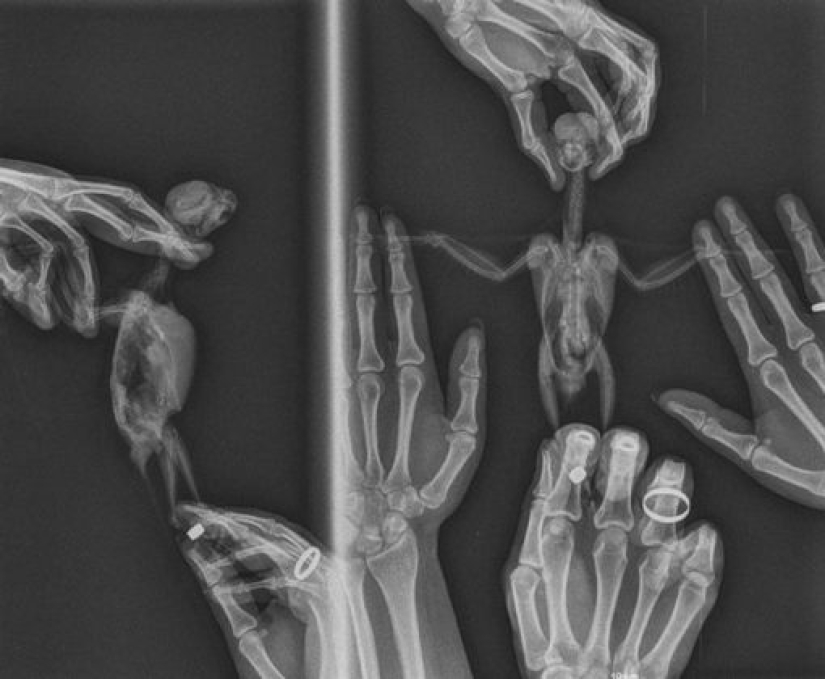

1. “Así es como se hace una radiografía de un loro. El pájaro está vivo y bien. El procedimiento fue realizado por un veterinario y estuvimos allí para ayudar a mantener a nuestra mascota”.